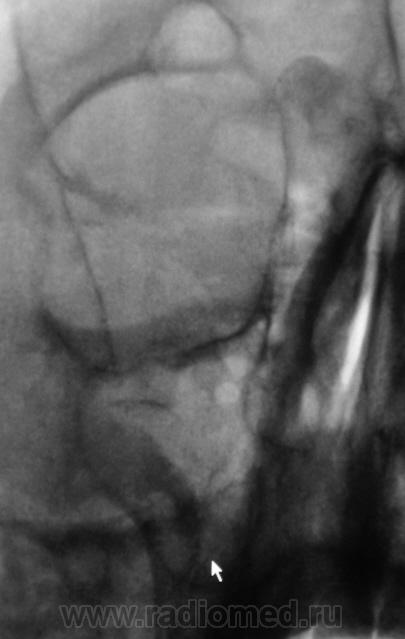

что-то плотное в правой лобной пазухе- остеома?

Образование правой лобной пазухи,пристеночное утолщение слизистой пр.гайморовой пазухи. Как всегда может помочь томограмма.

Остеома с типичной локализацией. Неосложненная.

Касательно пристеночного уплотнения справа в в/ч пазухе- вполне возможно суммационное искажение из-за неправильной укладки,с учетом клиники-я бы перестраховался и назначил томограмму(в идеале-малодозовый режим СКТ на ППН). Можно назначить контроль в динамике.